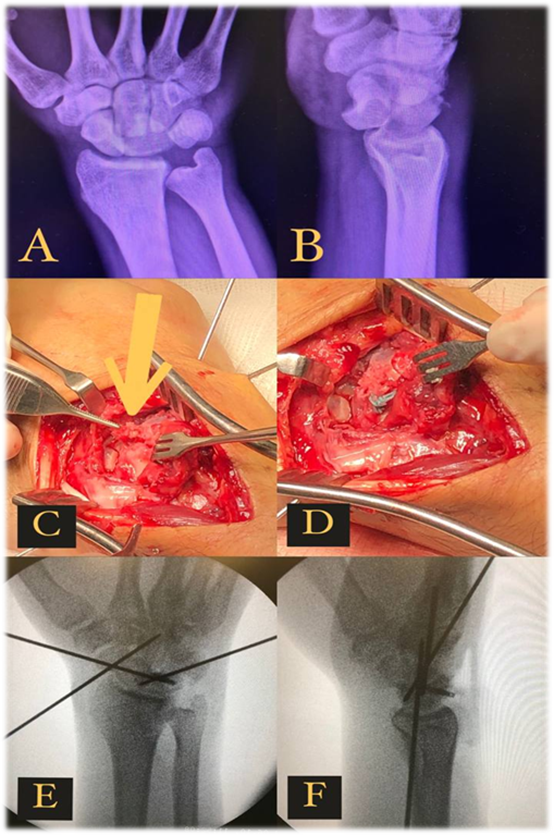

Perilunate Carpal Dislocation: A Case Report

Carlos Eduardo Seganfredo Camargo, Luigi Dal Pizzol Coberllini, Matheus Guanabara Fernandes, Rafael Oselame Guanabara

bjcr120